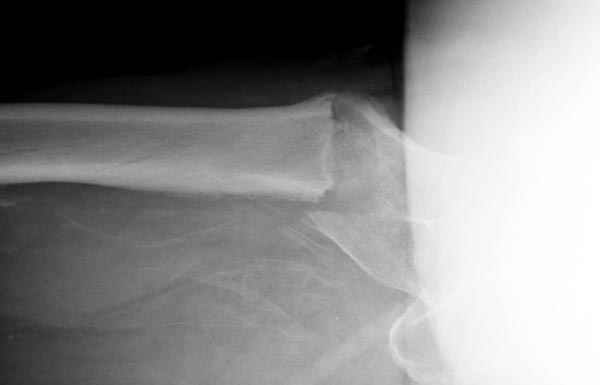

Здесь сканнированные снимки импланта и операционные снимки больной.